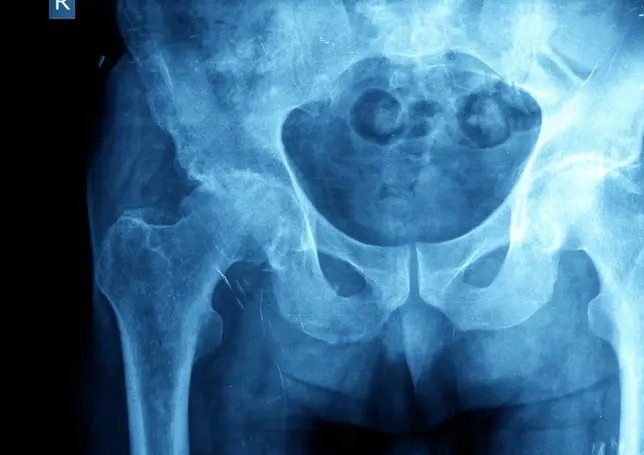

Coxartrosi